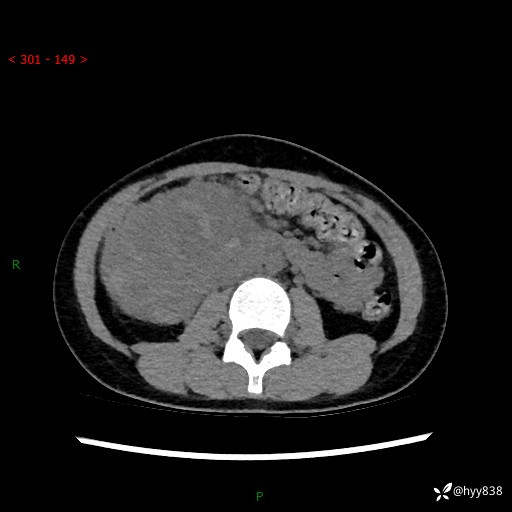

病例小姑娘,超声提示上腹部巨大包块。平扫就能轻松搞定的病变--结果公布

性别:女

年龄:13岁

简要病史:超声提示上腹部巨大包块

上腹部CT平扫

胰腺实性假乳头状瘤 (17)